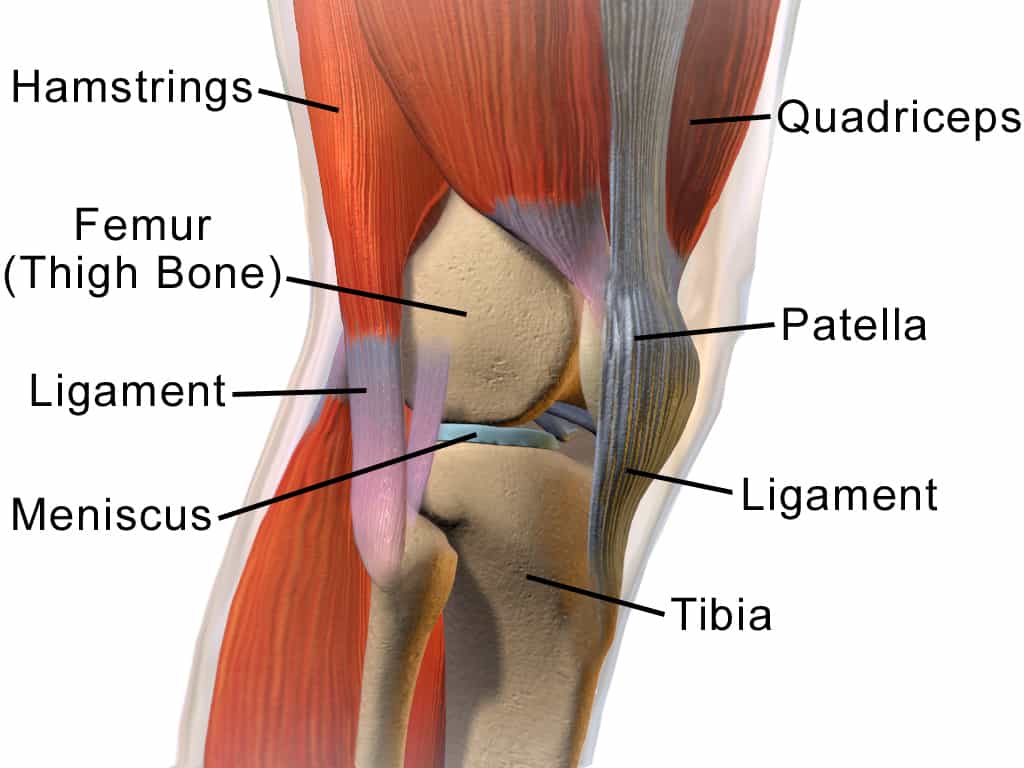

The largest joint in our body is the knee joint and one of the most easily injured joints. It is made up of bone, cartilage, tendons, and ligaments.